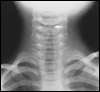

Cancer médullaire de la thyroïde avec métastases pulmonaires

Métastases multiples pulmonaires chez une patiente âgée de 47 ans atteinte de cancer médullaire sporadique. Le cancer médullaire est un cancer très lymphophile. La localisation préférentielle de ses métastases est d'abord cervicale, puis arrivent ensuite avec une fréquence comparable : le poumon (métastases pouvant persister plusieurs dizaines d'années), le foie et l'os.